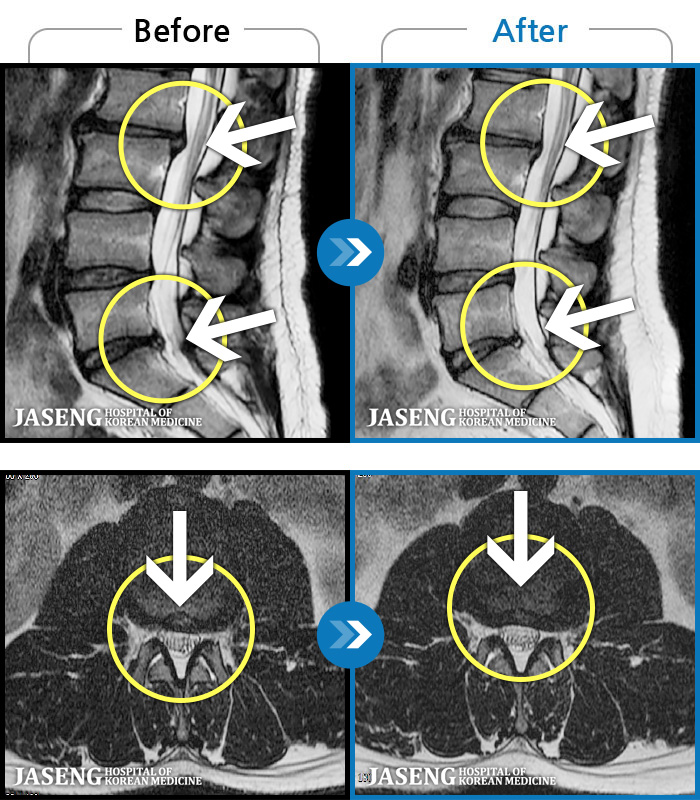

1,245 MRI ũ ʸ Ȯϼ.